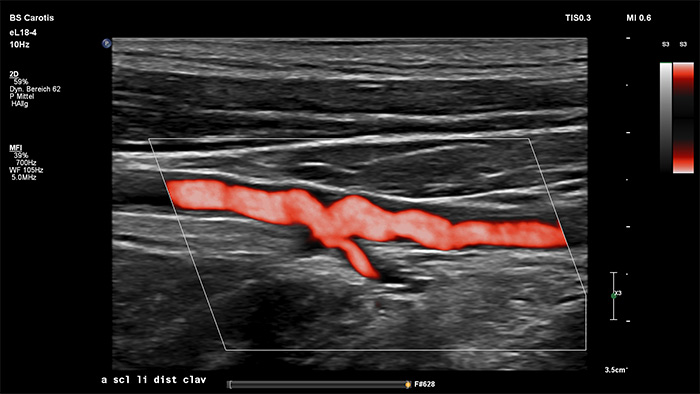

3D/4Dユーザーインタフェースは、フローデータを使用したVessel Cast生成機能も備えています。3D Vessel Cast生成機能により、フローを直接描出して、狭窄や蛇行状態を詳しく観察することができます。主なメリットとして、血管構造を高画質の3D/4Dで描出できるため、医療従事者の間で臨床的判断を促進し、患者本人による病状理解を促すコンサルテーションを強化する理想的なコミュニケーションツールとなる点が挙げられます。